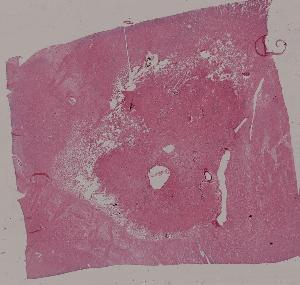

7.脑液化性坏死